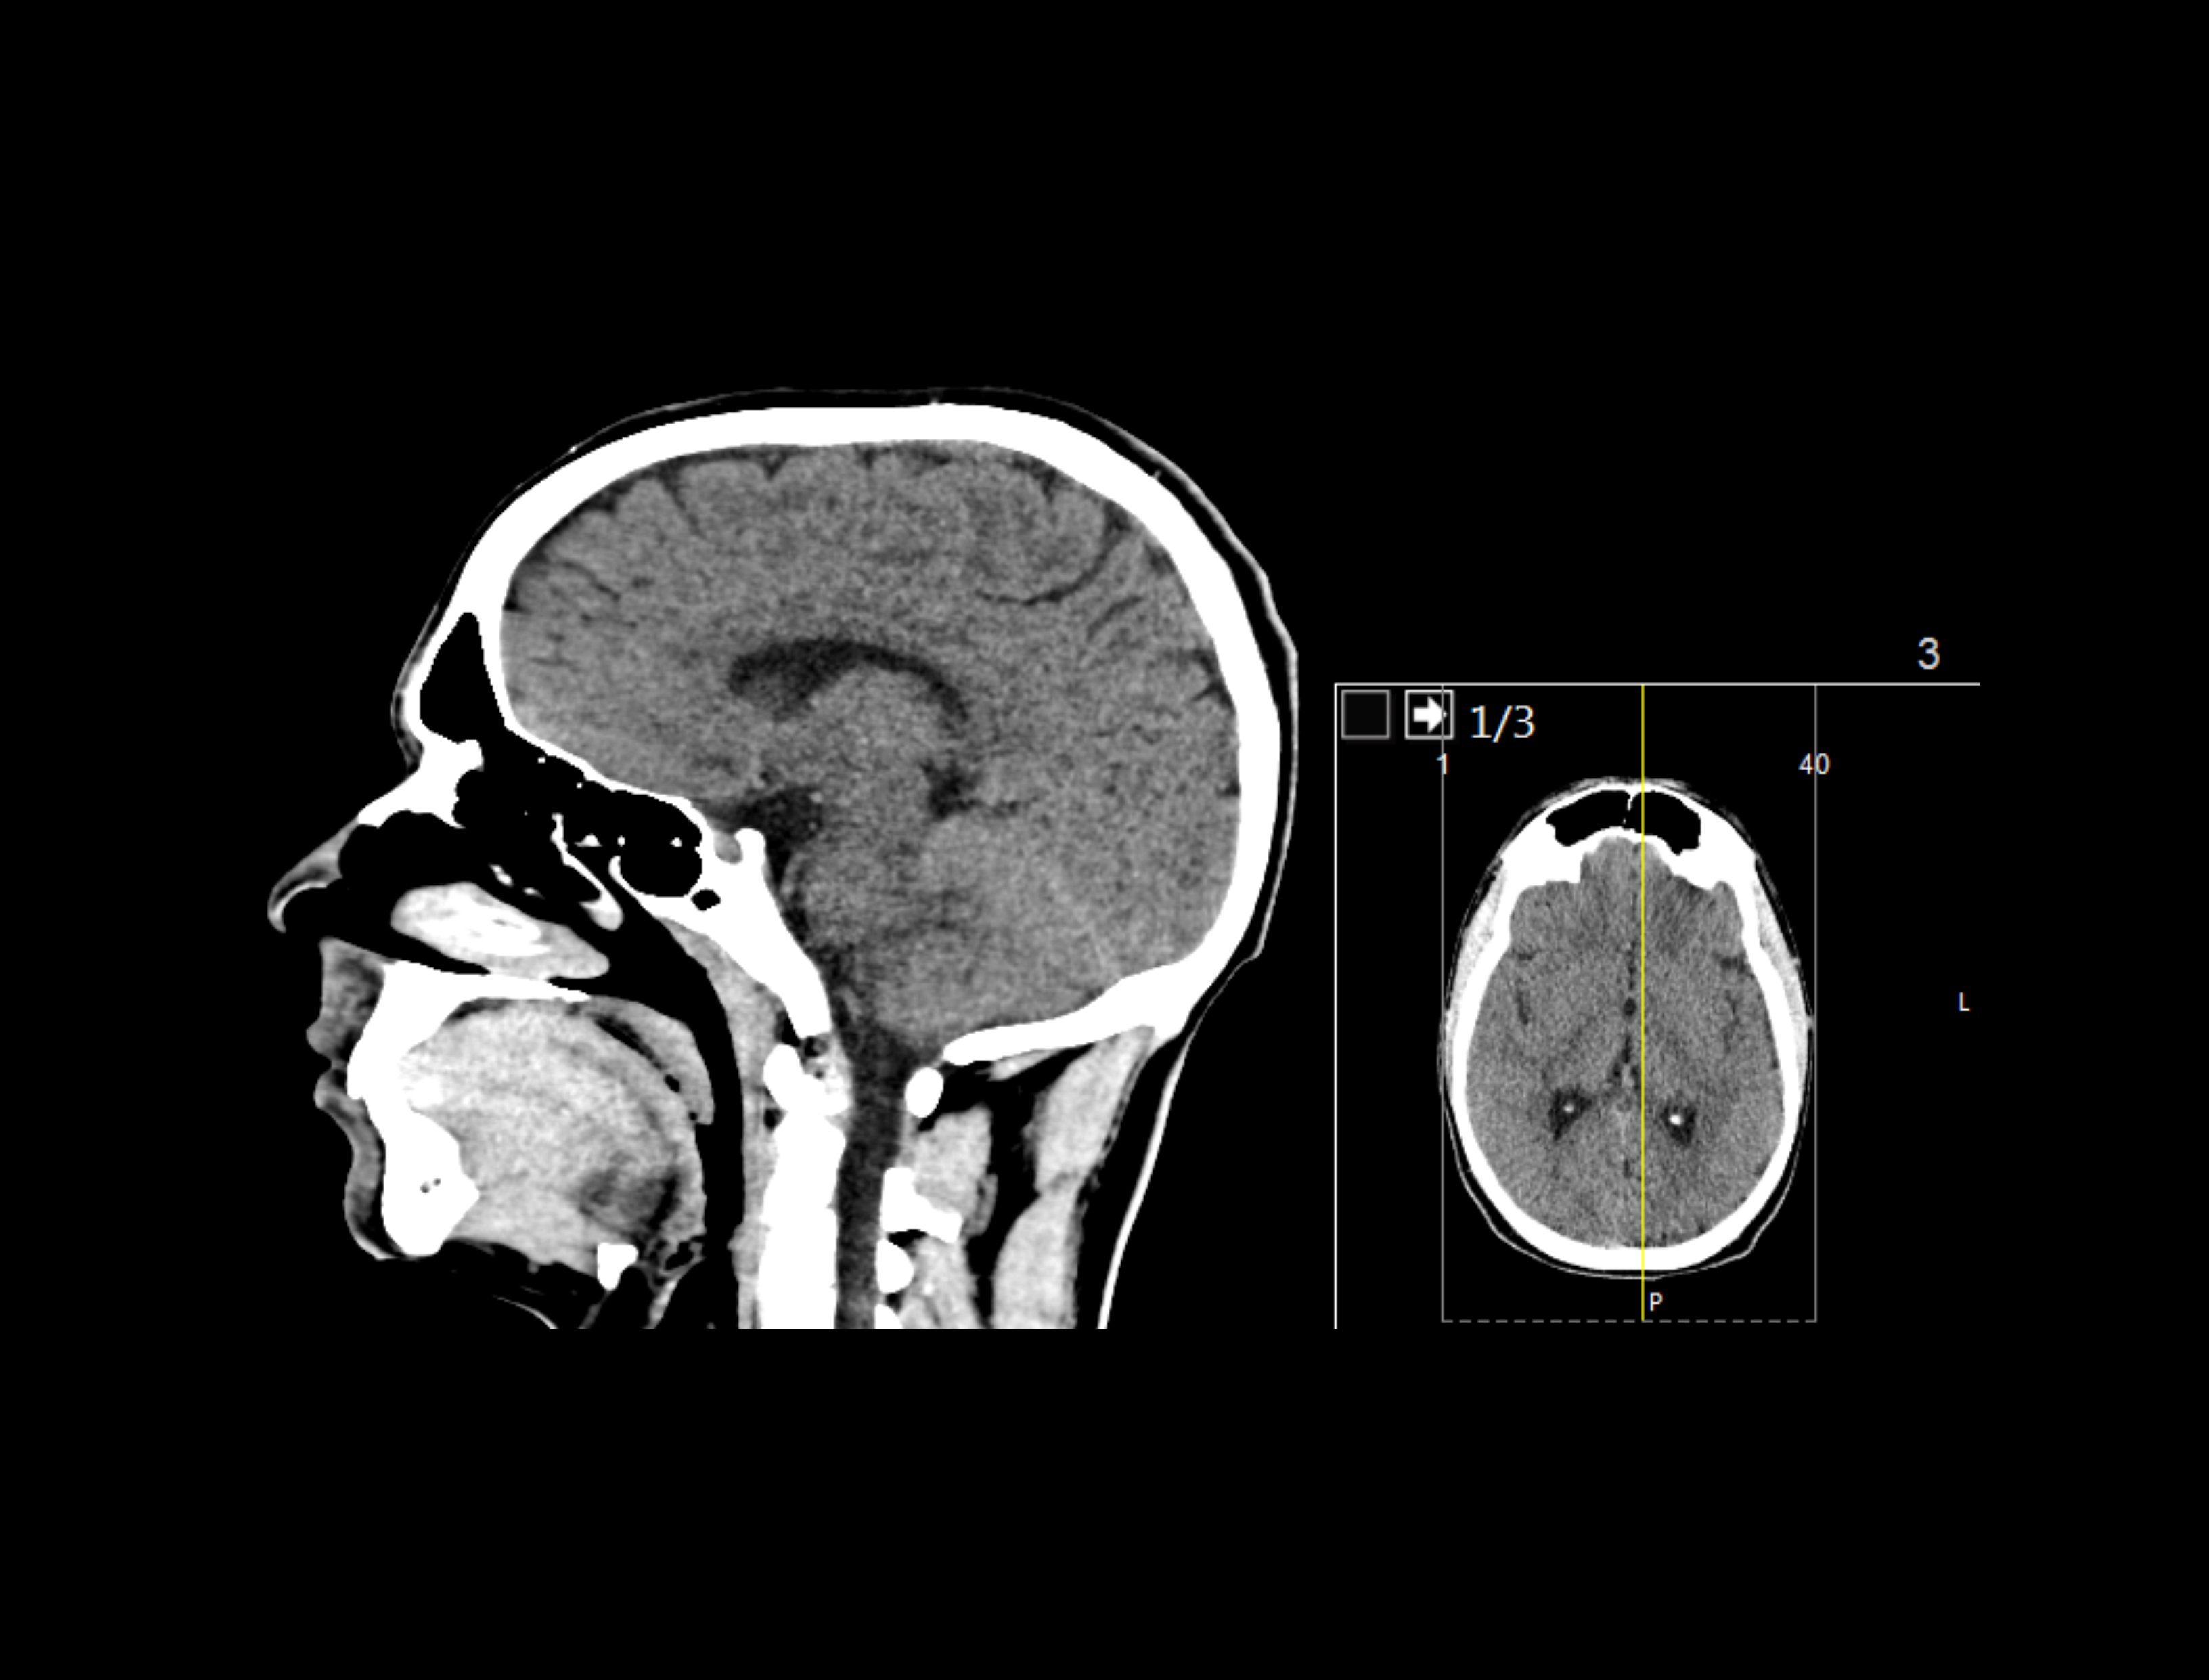

Alguns pacients van morir poc després d'arribar a la sala d'emergències, mentre que d'altres van romandre a l'hospital durant mesos. Tots els pacients tenien extenses investigacions clíniques i de laboratori, i alguns tenien ressonàncies magnètiques i tomografies computarizadas del seu cervell.

Per detectar qualsevol virus a les neurones i cèl·lules glials del cervell, els investigadors van utilitzar múltiples mètodes, inclosa la hibridació in situ d'ARN, que pot detectar ARN viral dins de cèl·lules intactes; anticossos que poden detectar proteïnes virals dins de les cèl·lules; i RT-PCR, una tècnica sensible per detectar ARN viral.

Ressonància magnéticaLa ressonància magnètica és una de les tècnica que han utilitzat per dur a terme la inverstigación

Malgrat la seva intensa recerca, els investigadors no van trobar evidència del virus a les cèl·lules cerebrals dels pacients. Encara que van detectar nivells molt baixos d'ARN viral per RT-PCR, això probablement es va deure a virus als vasos sanguinis o leptomeninges que cobreixen el cervell.